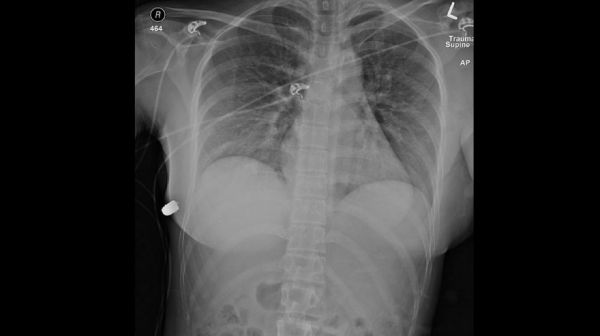

According to the report, the 30-year-old woman had been walking down a street in Toronto in 2018 when all of a sudden she felt “heat and pain in her left chest.” Upon looking down, she saw blood seeping out of her body and took herself to a local emergency room. She had an obvious gunshot wound located above her left nipple and was transferred to another trauma center.

Further examination revealed that the bullet had ended up in the woman’s lower right chest wall, underneath her breast. But she was otherwise remarkably fine. Doctors removed both of her silicone breast implants and saw that the bullet had clearly traveled through the left-side implant, which deflected it over to the right implant with enough force that it flipped the right implant upside down. The bullet then traveled through breast tissue before finally becoming embedded in her right chest.

(Image credit: McEvenue, et al/Plastic Surgery Case Studies)